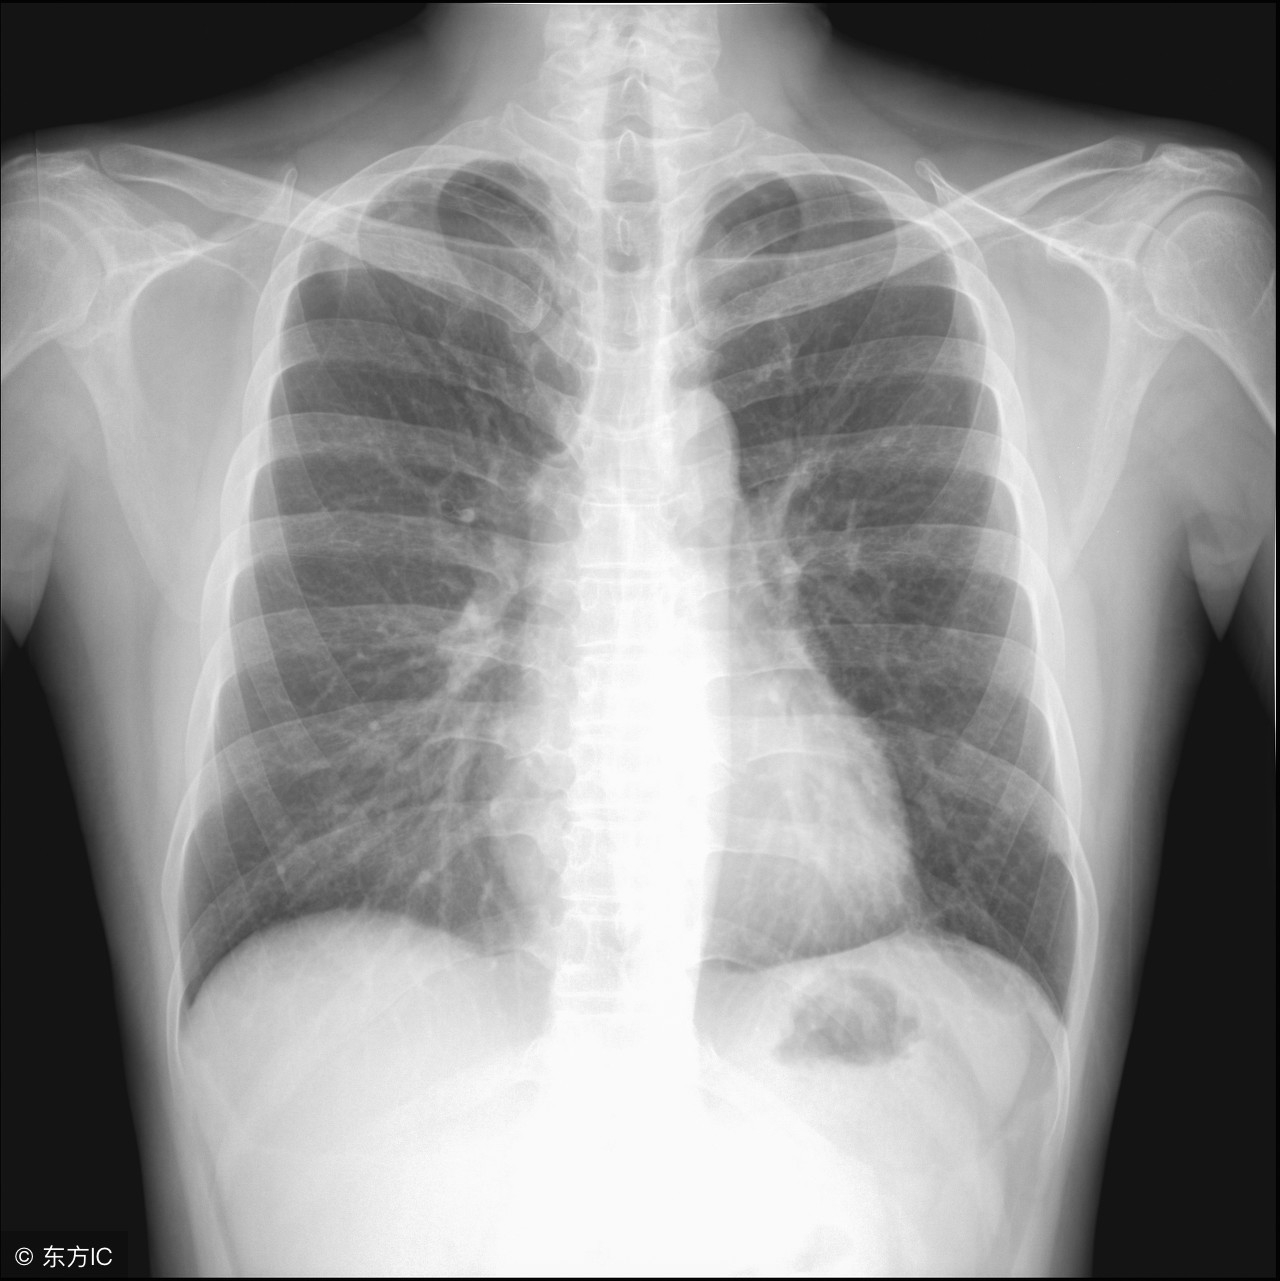

5、胸片

胸片也是体检的常备项目,可以有助于诊断肺部疾病和心源性疾病。